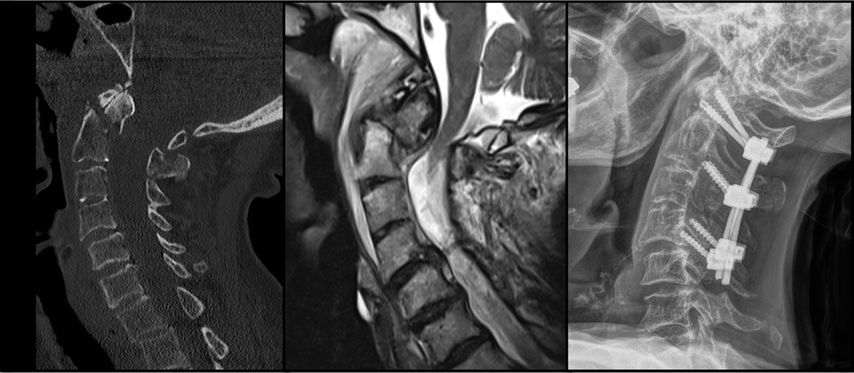

Abb. 2: CT, MRT und Versorgungsstrategie bei einer stark dislozierten Densfraktur Typ IIb mit begleitender Atlasbogenfraktur bei einer geriatrischen Patientin

Etwa 20% aller Wirbelkörperfrakturen im zervikalen Bereich sind Densfrakturen, die typischerweise eine bimodale Altersverteilung aufweisen: Ein kleiner Teil betrifft jüngere, sportlich aktive Männer – die Mehrheit der Betroffenen sind jedoch Frauen über 65 Jahre, welche auf Bodenniveau stürzen.10 Die Mortalität dieser Verletzungen kann mit jener von Schenkelhalsfrakturen im geriatrischen Kollektiv verglichen werden und beträgt rund 14% nach 30 Tagen sowie 44% nach zwei Jahren.11 Eine bestehende Arthrose des atlantoaxialen Gelenks, degenerative subchondrale zystische Veränderungen des Dens sowie eine verminderte Beweglichkeit der subaxialen Wirbelsäule bei geriatrischen Patient:innen erhöhen die mechanische Belastung auf die oberen Segmente der Halswirbelsäule.12 Dies begünstigt an der biomechanischen Schwachstelle – der Densbasis – das Auftreten einer Fraktur.10 Die Klassifikation nach Anderson und D’Alonzo, modifiziert durch Grauer, hat sich aufgrund ihrer prognostischen und therapeutischen Relevanz als Standard für die Einteilung der Densfrakturen etabliert.13,14 Typ I ist eine Abrissfraktur der Ligamenta alaria an der Densspitze, gilt als stabil und wird in der Regel konservativ behandelt. Typ II betrifft den Übergangsbereich des Dens zum Corpus und ist mit Abstand die häufigste Densfraktur, welche als potenziell instabil gilt. Grauer unterscheidet innerhalb der Typ-II-Frakturen die Subtypen IIa (transversaler Frakturverlauf), IIb (Frakturverlauf von anterosuperior nach posteroinferior) und IIc (von anteroinferior nach posterosuperior). Typ III sind Frakturen des Corpus der Axis, welche in der Regel konservativ behandelt werden können. Die Behandlung der Typ-II-Densfraktur bei älteren Patient:innen wird nach wie vor kontrovers diskutiert. Während einige Studien eine operative Versorgung zur Verbesserung der Fusionsrate sowie der Lebensqualität empfehlen, weisen andere darauf hin, dass auch eine konservative Therapie bei geriatrischen Patient:innen ein zufriedenstellendes funktionelles Ergebnis und eine geringe Komplikationsrate ermöglichen kann.11 Die Operationsindikation ergibt sich bei nachgewiesener Instabilität oder bei neurologischer Verschlechterung, etwa infolge einer Myelopathie. Zu berücksichtigen ist, dass bei konservativer Behandlung das Risiko einer Pseudarthrose mit daraus resultierenden chronischen Beschwerden sowie einer möglichen progredienten neurologischen Verschlechterung besonders bei aktiven älteren Patient:innen erhöht ist. Die Blutversorgung des Dens erfolgt überwiegend durch ein Gefäßnetz aus aufsteigenden Ästen der A. vertebralis, das an der Spitze des Dens eine Anastomose und an der Basis einen Gefäßplexus bildet. Diese Gefäßversorgung wird bei Typ-II-Frakturen häufig unterbrochen, was die Knochenheilung negativ beeinflusst.15 Für die Beurteilung der Instabilität gelten folgende Kriterien: eine Dislokation von mehr als 5mm, ein Frakturspalt von über 2mm oder ein kyphotischer Winkel von mehr als 11°.10 Frische IIa- und IIb-Densfrakturen eignen sich für eine ventrale Schraubenosteosynthese. Die dorsale Fusion wird hingegen für IIc-Frakturen, Trümmerbrüche des Dens, stark dislozierte Frakturen sowie bei bereits bestehender Pseudoarthrose bevorzugt.15 Der Halo-Fixateur wird bei geriatrischen Patient:innen heute nicht mehr empfohlen,5,10,11,15 da die Komplikationsrate mit über 30% sehr hoch ist. Häufige Komplikationen umfassen Aspirationspneumonien, Infektionen der Pin-Stellen sowie Druckstellen, Schluckbeschwerden und eine insgesamt erhöhte Mortalität.